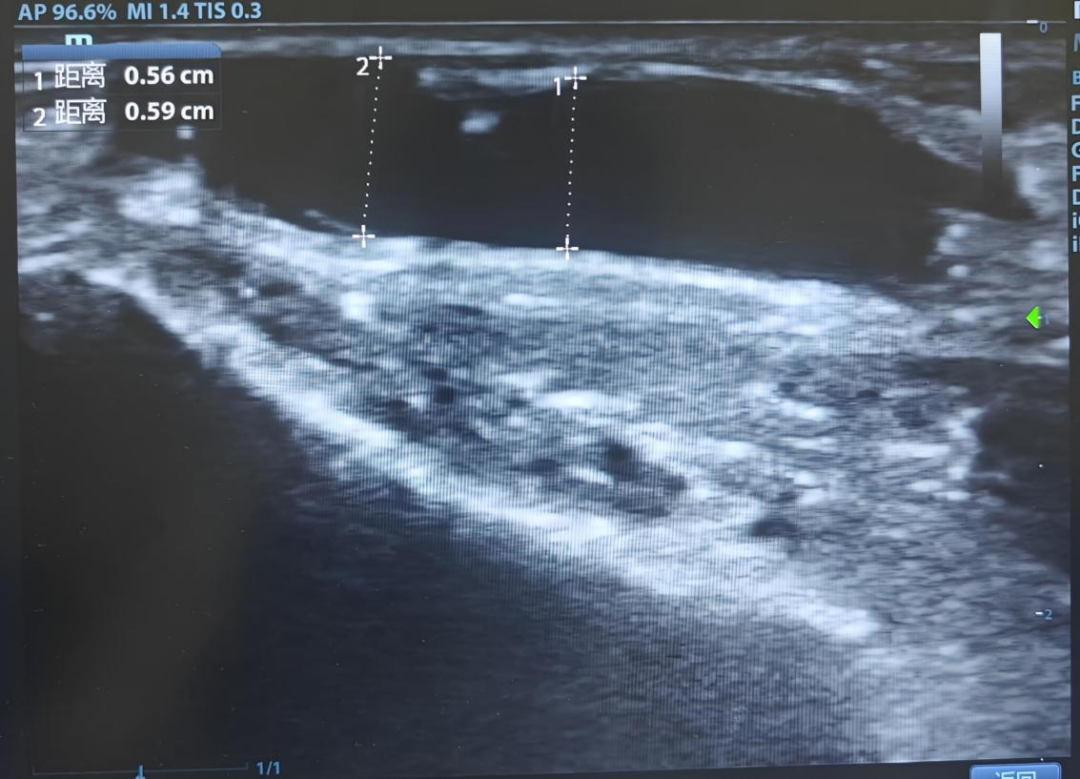

在评估造瘘后头静脉状态方面,超声检查是首选方式,它无创、无辐射,还能反复检查。检查时,超声医师通过二维超声,能清晰看到头静脉的走行、管壁厚度、管腔内径,精准测量血管增粗程度,判断头静脉有无狭窄、血栓、内膜增生、静脉瓣功能异常等问题;同时结合彩色多普勒超声,实时观察头静脉内血流方向、血流充盈情况,检测血流速度与血流量,全面评估血管通畅性与血流动力学状态。

临床实践中,造瘘后头静脉能否正常增粗,直接关系到内瘘是否成熟、能否投入透析使用。超声检查既能直观判断血管增粗是否达标,也能及时发现各类异常:如果头静脉增粗不足、管径太细,说明内瘘成熟不佳,无法满足透析需求,医师会及时指导患者进行功能锻炼或采取其他临床干预措施;如果血管出现狭窄、血栓等问题,会直接导致透析血流量不足,影响透析效果,甚至让内瘘失去功能,而超声能早期找到病变位置、判断病变轻重,为临床制定溶栓、介入等治疗方案提供准确依据。